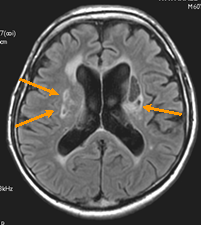

ラクナ梗塞

(lacunar infarction)